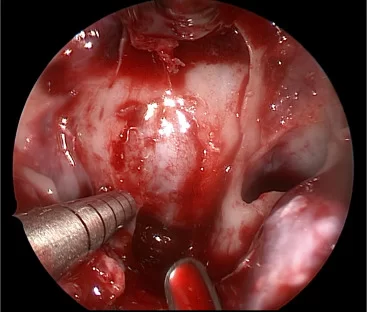

- Ο χειρουργός εισάγει το ενδοσκόπιο σε ένα ρουθούνι και το προωθεί το στο πίσω μέρος της ρινικής κοιλότητας. Το ενδοσκόπιο είναι ένα λεπτό όργανο με φως και κάμερα. Το βίντεο από την κάμερα προβάλλεται σε μια οθόνη (εικόνα 2). Ο χειρουργός περνά τα εργαλεία μέσα από το ρουθούνι ενώ παρακολουθεί την οθόνη. Χρησιμοποιώντας ειδικά εργαλεία, ο χειρουργός ανοίγει το πρόσθιο τοίχωμα του σφηνοειδούς κόλπου (εικόνα 2).